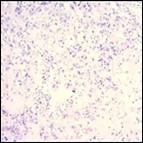

Multinodular tumour architecture is constituted by miniature, uniform, elliptical or spindle-shaped cells with scanty, eosinophilic, finely vacuolated cytoplasm and miniature, regular or hyperchromatic nuclei. Myxoid tumour matrix is envelops neoplastic cells configuring cords and strands. Nuclear pleomorphism is absent. Tiny foci of necrosis with focal chondroid differentiation may ensue6. Meningo-endothelial cells, physaliferous cells, rhabdoid cells, ductal differentiation and anaplastic cellular dedifferentiation is usually absent. Myoepithelial carcinoma displays nuclear atypia, elevated mitotic rate and extensive foci of tumour necrosis5. Figure 1, Figure 2, Figure 3, Figure 4, Figure 5, Figure 6, Figure 7, Figure 8.

Figure 2.Parachordoma delineating clusters of vacuolated, spherical cells with acidophilic cytoplasm, uniform nuclei and an immune non reactive CD34- 13.